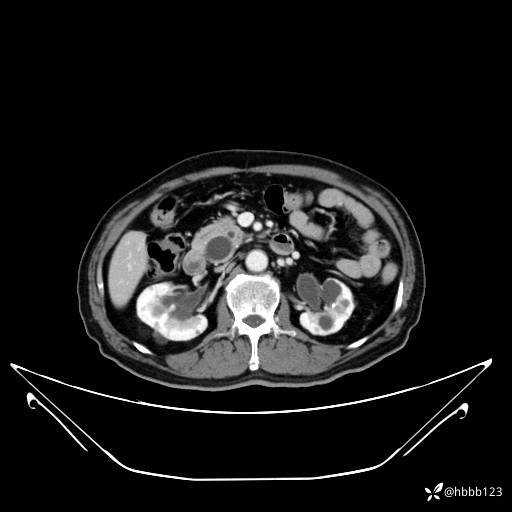

动脉期: